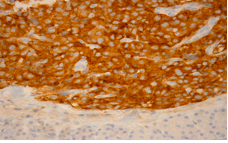

Figure 5a HE 10x: Low –power photomicrograph demostrating a neuroendocrine tumor. The tumor shows solid, ribbonlike, and acinar growth patterns.

Figure 5b HE 40x: Higher magnification showing monomorphous cell, large nuclei and small nucleoli as well as inconspicuous cytoplasma and fine cromatina. Mitoses are rare.

Figure 5c Low antibody staining against Ki-67 (nuclear protein present during all active phases of cell cycle and absent from resting cells).

Figure 5d Intense staining against synaptophysin (citoplasmatic protein located in neurons and neuroendocrine tumors).